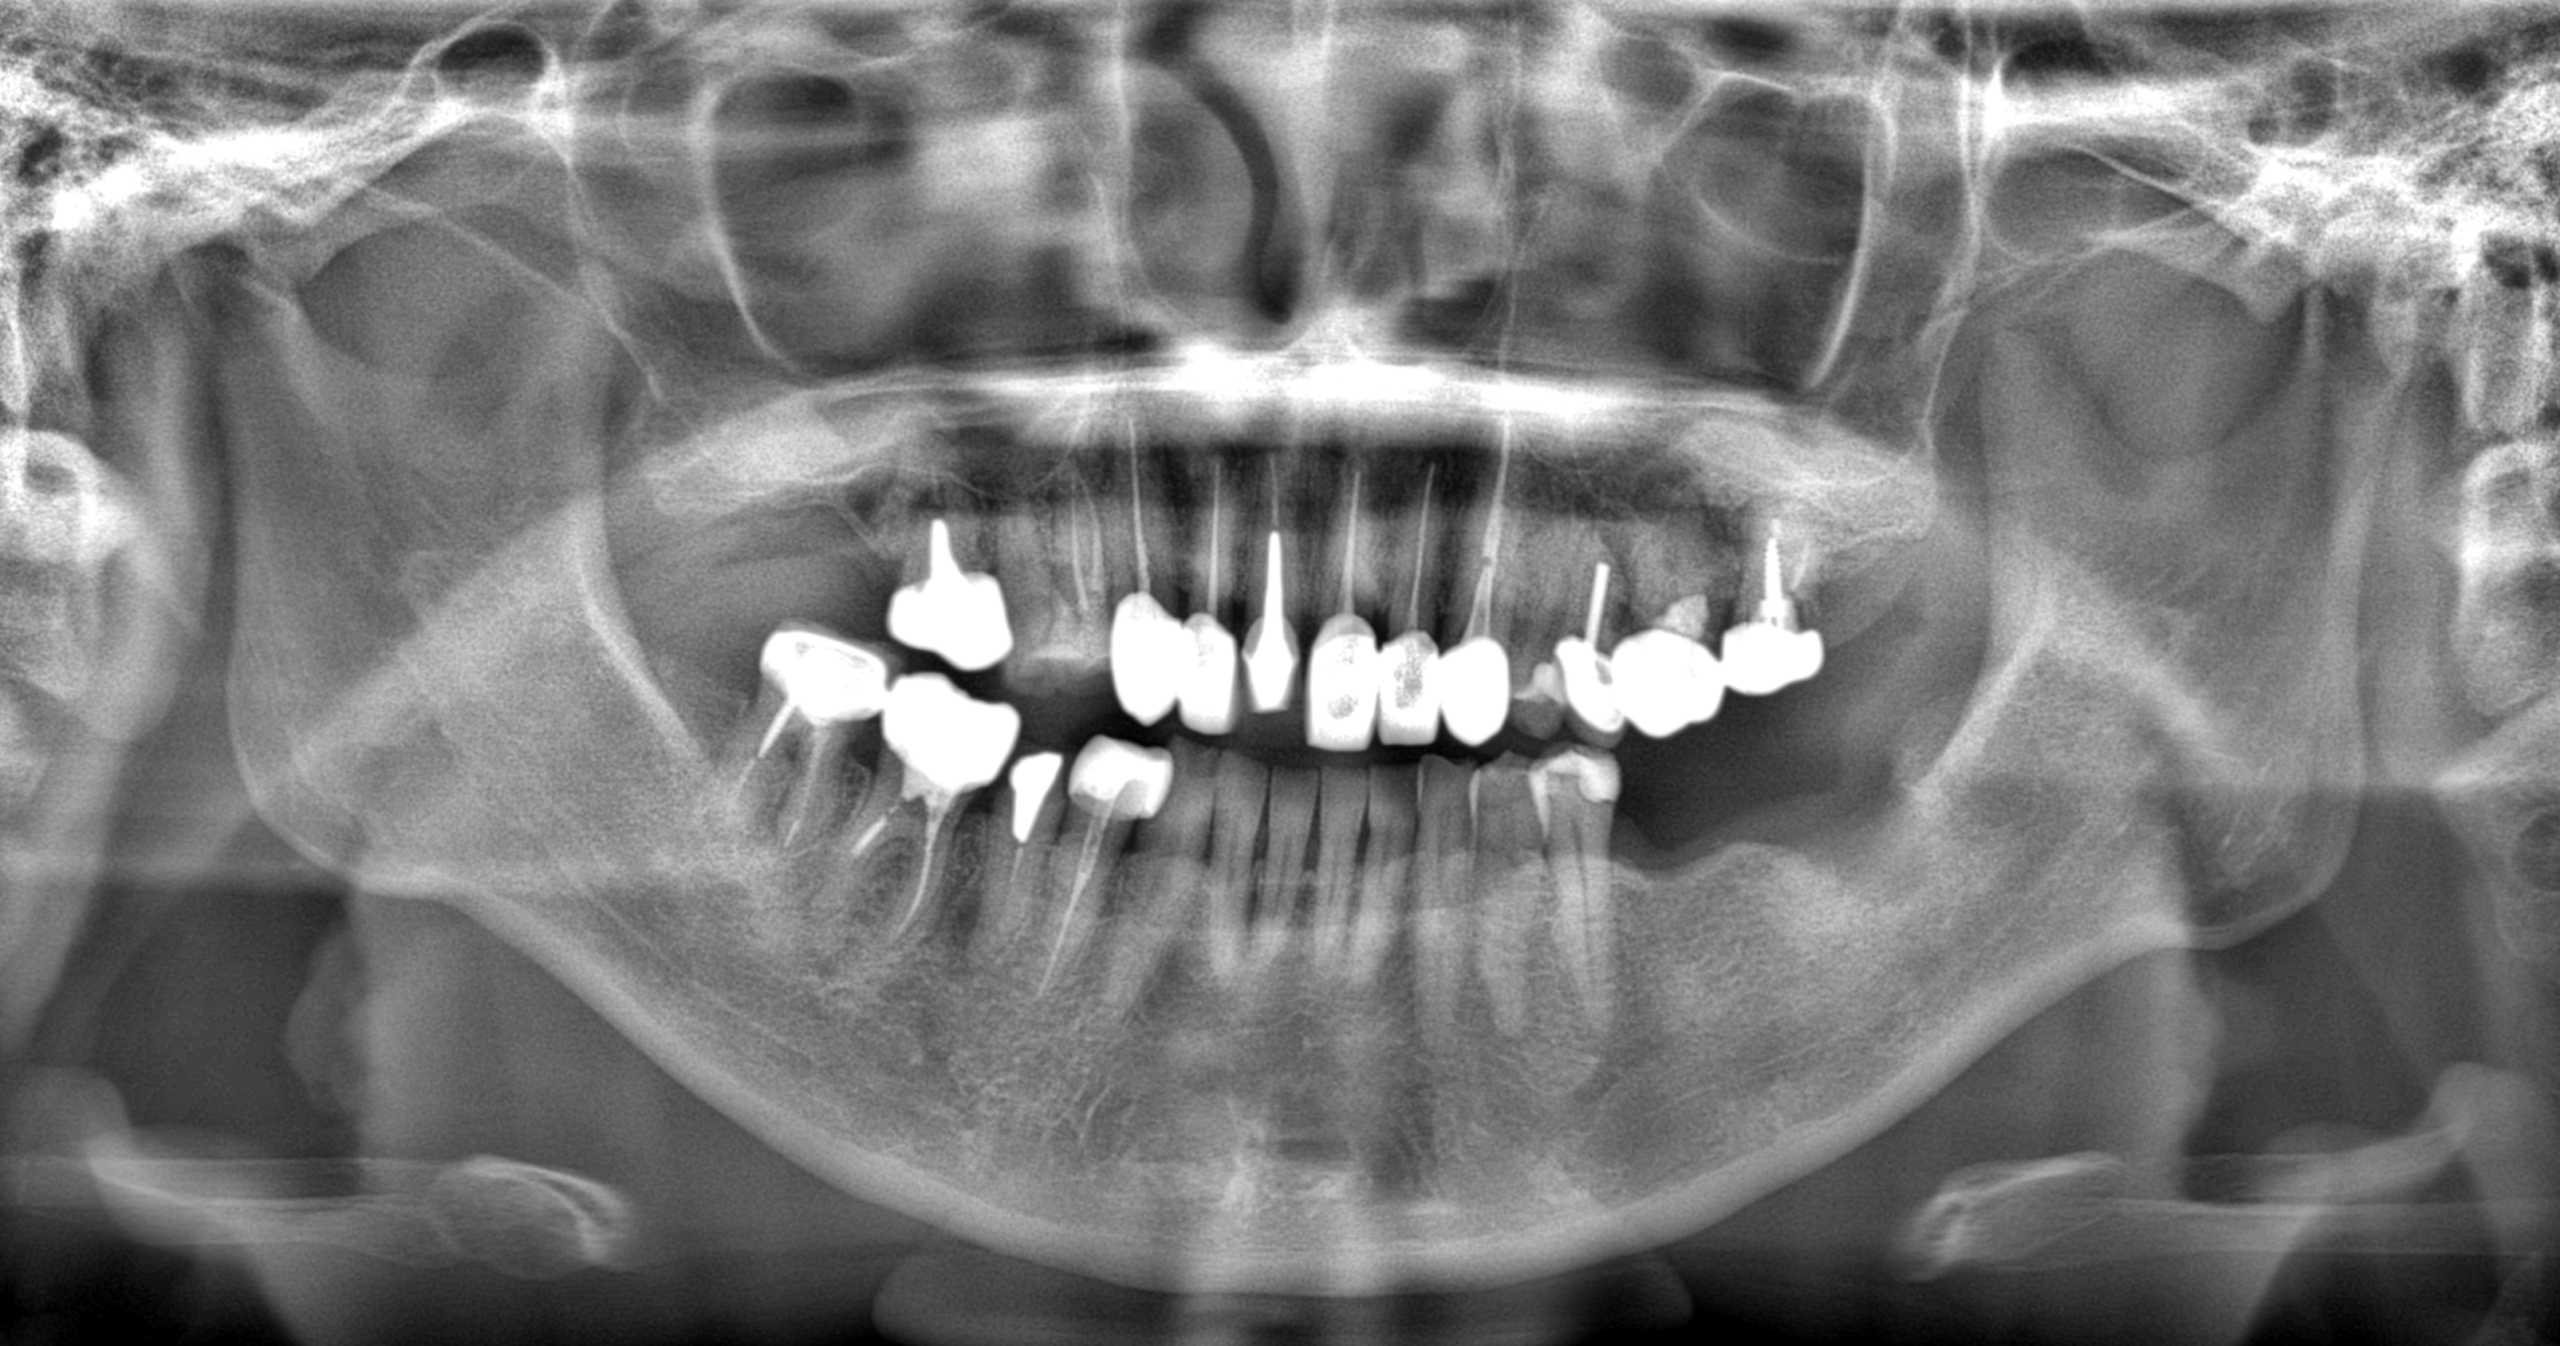

レントゲンなどでその歯を細かく診断すると、歯が縦にヒビが入っており再治療をしても治癒させることは難しいことを患者様に伝えました。

ただ、周囲の骨の吸収はあまりなく、抜歯即時埋入が可能な状態であったため、その旨をお伝えし、インプラント治療に同意を得ました。

手術は抜歯と同時にサージカルガイド(手術用マウスピース)を用いて、予定していた埋入ポジションにインプラントを埋入しました。

術後のレントゲンでも問題はなく、術後4ヶ月後に歯が入りました。